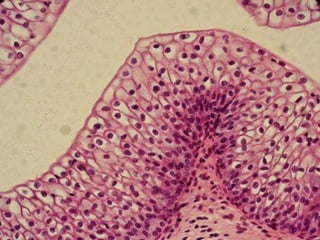

STRATIFIED SQUAMOUS EPITHELIUM

 It consists of a variable number of cells layer which

exhibit transition from a cuboidal basal layer to a

flattened surface.

 Basal layer divide continuously.

 Well adapted to withstand abrasion since loss of

surface cells does not compromise the underlying

tissue.

 Nuclei become progressively condensed (pyknotic)

and flattened, before ultimately disintegrating.

STRATIFIED SQUAMOUS NONKERATINISED

EPITHELIUM

Flattened with nuclei.

Moist superficial cells are living.